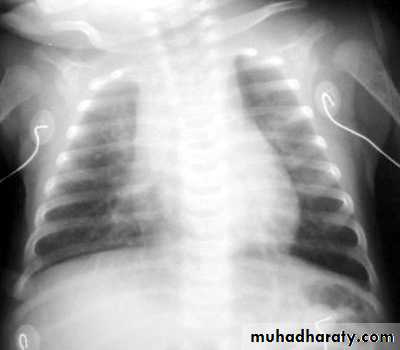

CXR: segmental lung atelectasis. Perihilar infiltrates are common and are similar to what is seen in viral pneumonia.

"shaggy heart" on CXR in a patient with Bordetella pertussis pneumonia.